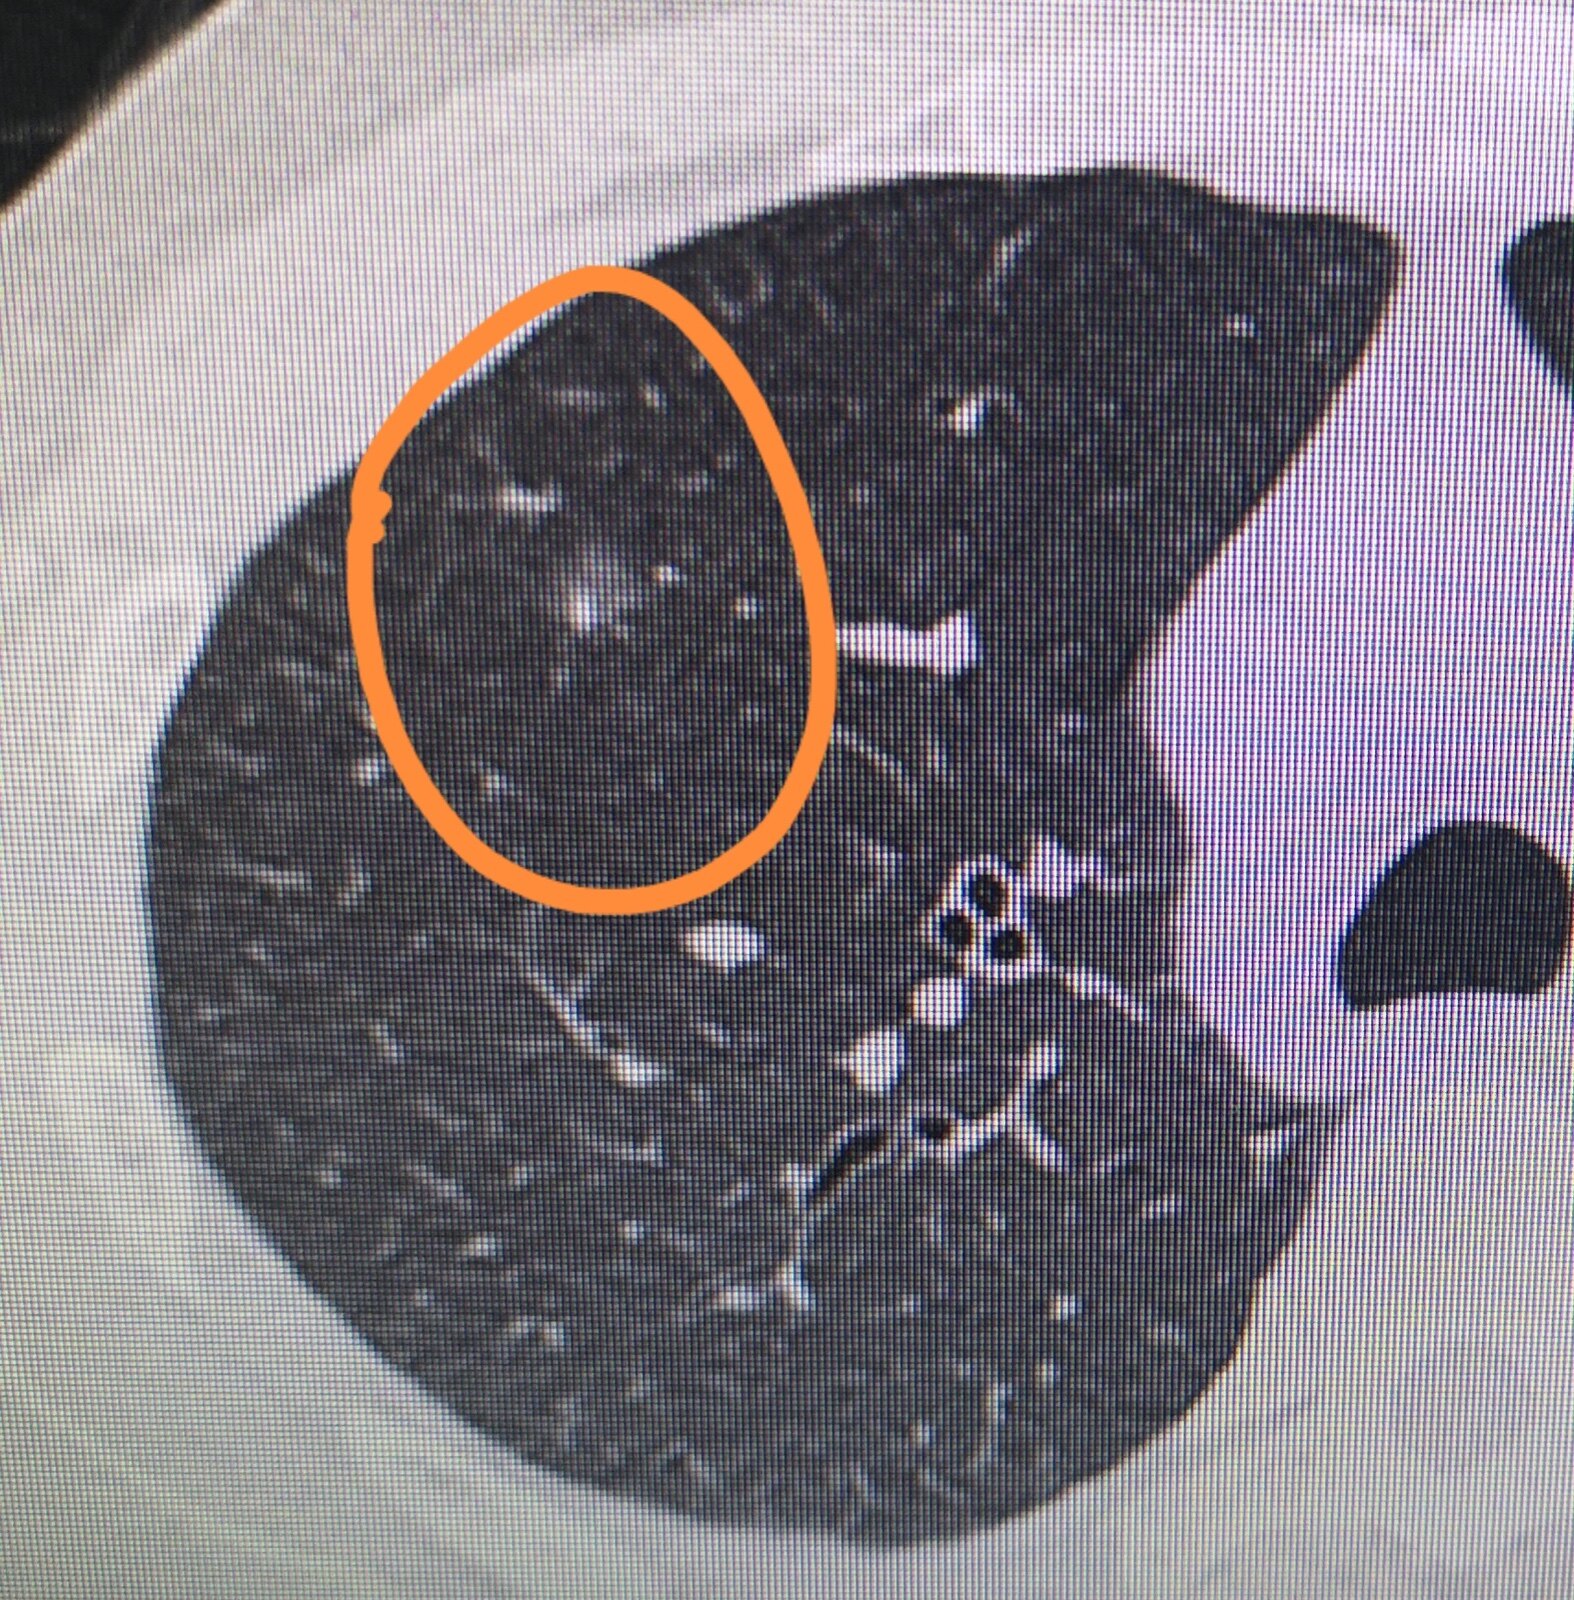

肺结节是一个影像学上的概念,它通常是指在进行影像学检查时边界清楚、不透明、直径≤3CM单发或多发肺部结节病变。

这里要说明的是,之所以特意指出3CM是因为它是区分肺结节与肺肿物的临界点,即>3CM的结节我们将其称之为肿物,≤3CM的我们将其称为肺结节。为了方便诊治,我们将肺结节再细分为:微小结节(≤5mm),小结节(5mm~10mm),大结节(10mm~30mm)。